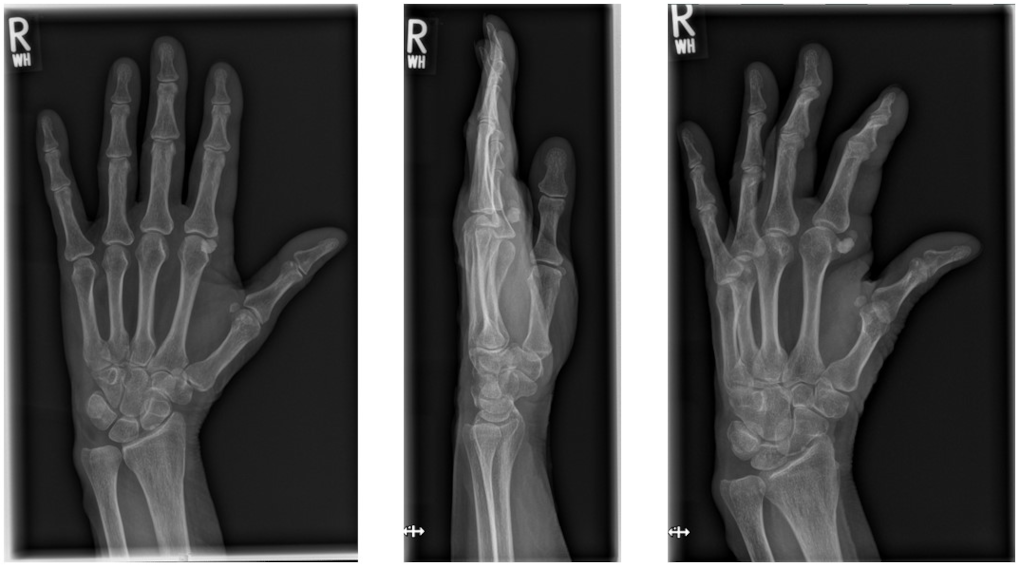

We performed a radiographic examination of the affected hand, followed by a contrast-enhanced CT scan. Based on the imaging findings, avascular necrosis of the sesamoid bone at the MCP joint was suspected (Figure 2 [Fig. 2], Figure 3 [Fig. 3] and Figure 4 [Fig. 4]).

Figure 2: Preoperative X-ray of the right hand in three planes